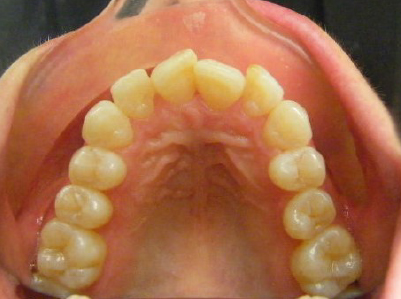

Patient 4: Upper and lower crowding and a deep overbite.